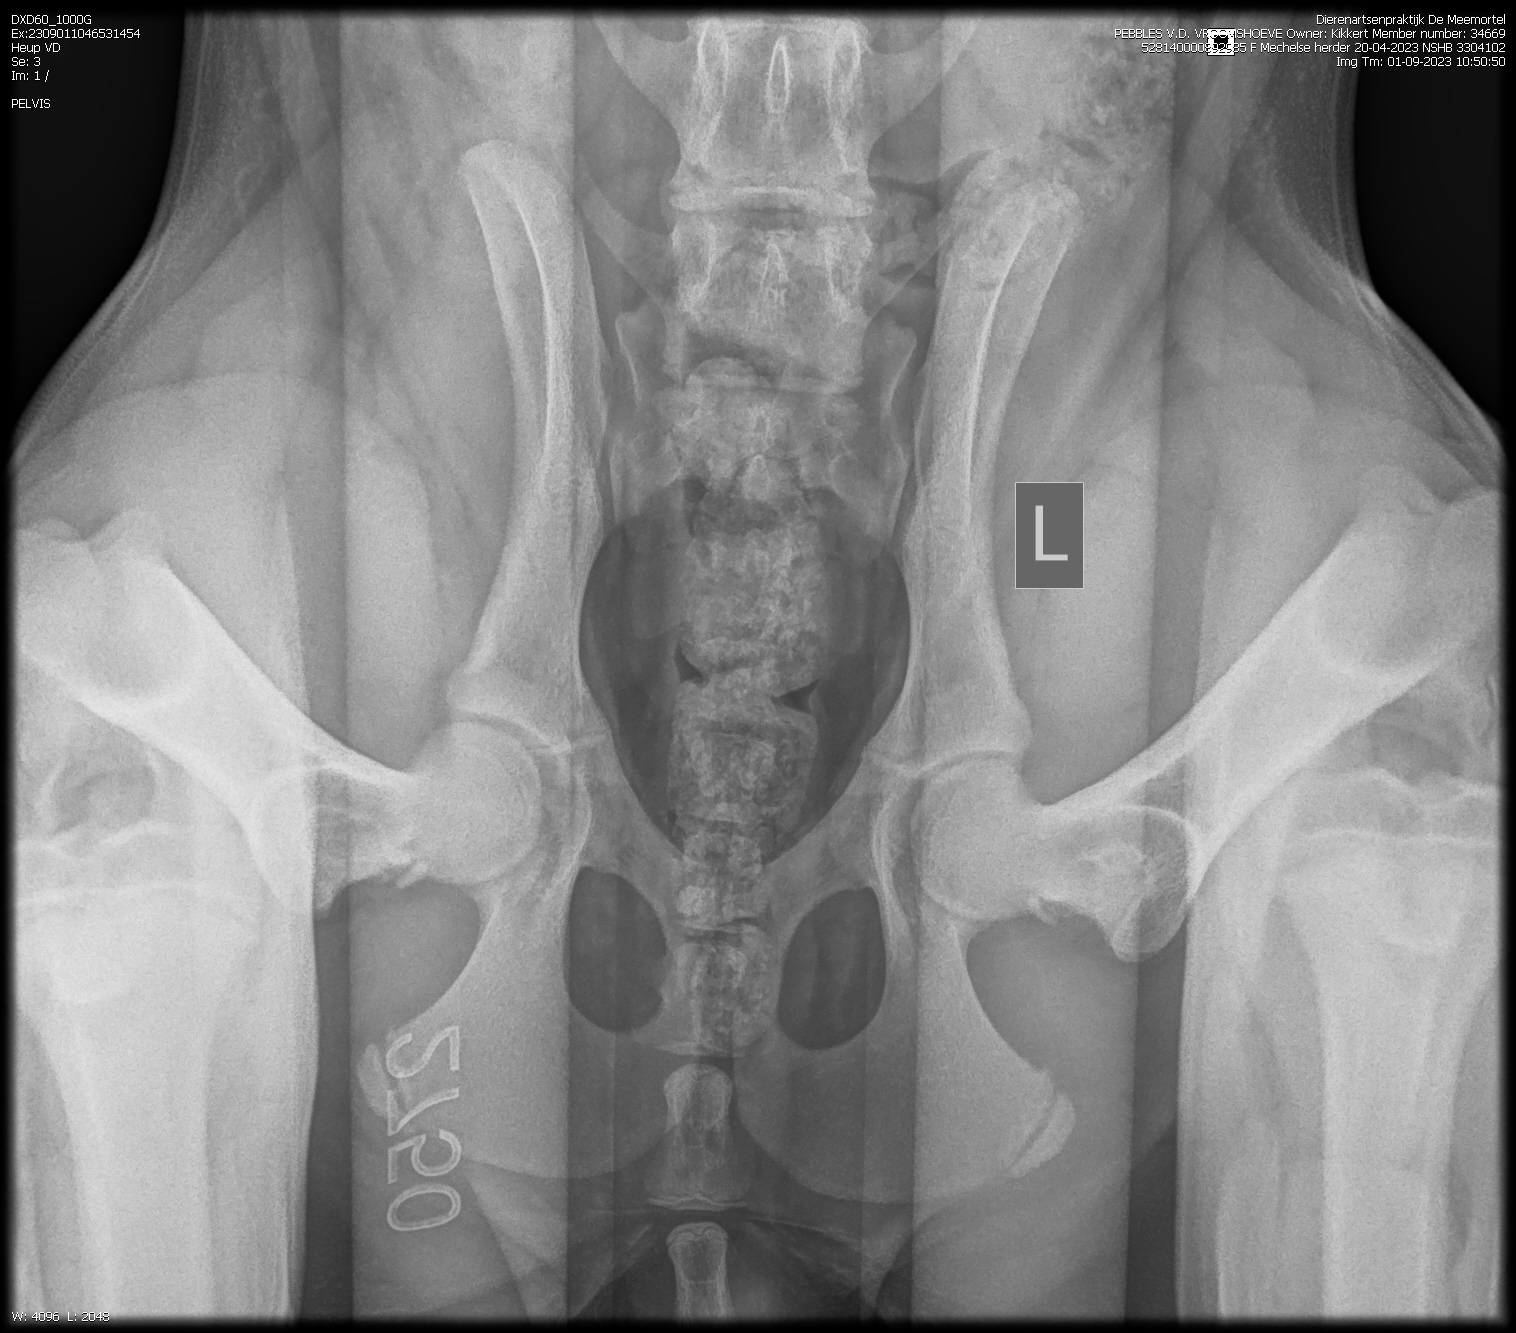

PennHip : Rechts DI 0.19 Links DI 0.16